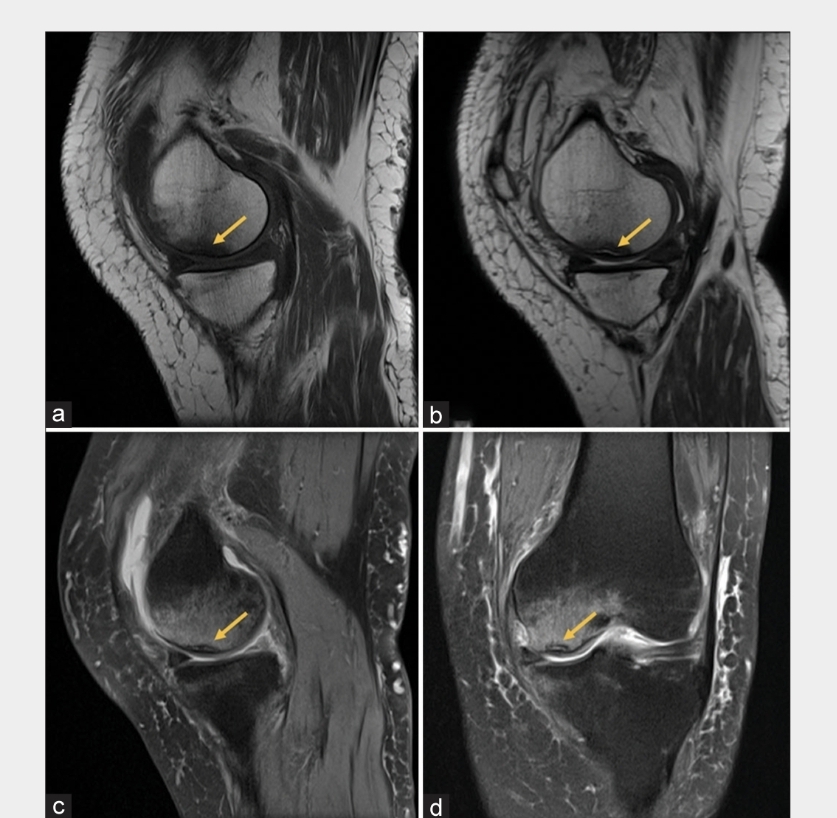

엑스레이상에서는 이상이 없게 보이지만 ct나 mri촬영을 하면 미세하게 골절된걸 확인할수있다.

대부분 스트레스성 골절이 많이 생기는 부위는

무릎, 발등, 종아리, 발목,대퇴골,골반 등이 가장흔하게 발생한다.